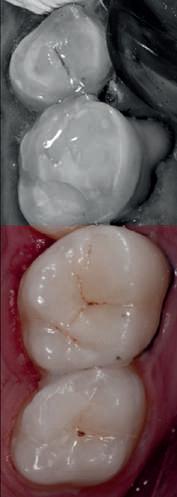

HYBRID COMBINATION RESTAURATIONS

Vonlay-uri: o alternativă conservatoare estetică la coroanele cu acoperire totală